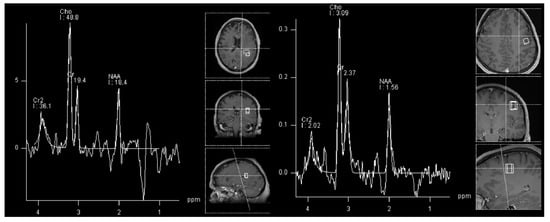

- Donia, M.; Abougabal, A.; Zakaria, Y.; Farhoud, A. Role of proton magnetic resonance spectroscopy in diagnosis of pilocytic astrocytoma in children. Alex. J. Med. 2012, 48, 131–137. [Google Scholar] [CrossRef]

- Porto, L.; Kieslich, M.; Franz, K.; Lehrnbecher, T.; Zanella, F.; Pilatus, U.; Hattingen, E. MR spectroscopy differentiation between high and low grade astrocytomas: A comparison between paediatric and adult tumours. Eur. J. Paediatr. Neurol. EJPN Off. J. Eur. Paediatr. Neurol. Soc. 2010, 15, 214–221. [Google Scholar] [CrossRef]

- Hasan, A.M.; Hasan, A.; Megally, H.; Khallaf, M.; Haseib, A. The combined role of MR spectroscopy and perfusion imaging in preoperative differentiation between high- and low-grade gliomas. Egypt. J. Radiol. Nucl. Med. 2019, 50, 72. [Google Scholar] [CrossRef]

- Shakir, T.; Fengli, L.; Chenguang, G.; Chen, N.; Zhang, M.; Shaohui, M. 1H-MR spectroscopy in grading of cerebral glioma: A new view point, MRS image quality assessment. Acta Radiol. Open 2022, 11, 205846012210770. [Google Scholar] [CrossRef]